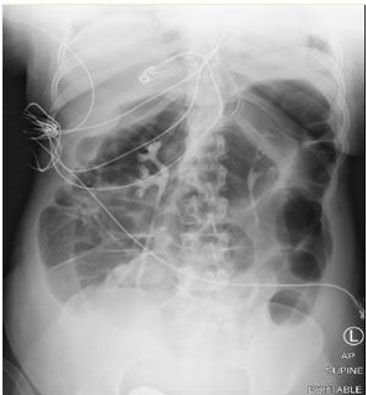

On postoperative day 1, the patient was extubated. Following extubation, the patient was noted to be dyspneic with increased work of breathing requiring bilevel positive airway pressure (BiPAP) and subsequent reintubation. Further evaluation revealed mild range hypertension and transaminitis [aspartate aminotransferase (AST) 78, alanine aminotransferase (ALT) 65], now consistent with preeclampsia with severe features. On postoperative day 2, a nicardipine drip was initiated given severe range hypertension which continued until postoperative day 5. The patient remained intubated however developed abdominal distention with abdominal X-ray revealing an ileus (Figure 2). Workup by the gastroenterology team revealed colonic pseudo-obstruction requiring nasogastric tube and rectal tube placement for decompression. By postoperative day 4, the patient was again extubated, but within 12 hours, she developed significant work of breathing requiring a third intubation. Rheumatology and neurology consultations were obtained, and preliminary workup, including initial acetylcholine receptor antibodies, returned negative. By postoperative day 6, the patient developed progressive neck and bulbar muscle weakness with head droop to the right side and drooling. A discussion occurred among the care teams regarding the propensity for autoimmune diseases to present or flare in the postpartum period. Given concern for myasthenia gravis, a pyridostigmine challenge was initiated with 60 mg three times daily for five days and the patient was able to transition to continuous positive airway pressure (CPAP). With limited improvement in muscle and respiratory weakness, the pyridostigmine was discontinued on postoperative day 12. By hospital day 15, muscle-specific kinase antibody resulted positive which confirmed a diagnosis of myasthenia gravis thus pyridostigmine was restarted and prednisone was initiated. The patient’s respiratory status and strength improved with resolution of ileus. She was discharged home on hospital day 21 with a tracheostomy collar.

Figure 2: Radiograph of colonic ileus, POD #2.